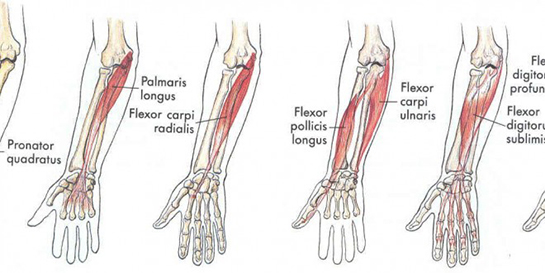

Bu tür yaralanmalar, genellikle ani ve beklenmedik durumlar sonucunda meydana gelir. Yaralanmanın ciddiyeti, kesik alanının derinliğine, kanamanın miktarına ve sinir veya tendonların etkilenip etkilenmediğine göre değişiklik gösterir. Kesilmiş Bilek Tedavi Aşamaları Kesilmiş bilek tedavisi, genellikle üç ana aşamadan oluşur: acil müdahale, cerrahi onarım ve rehabilitasyon.